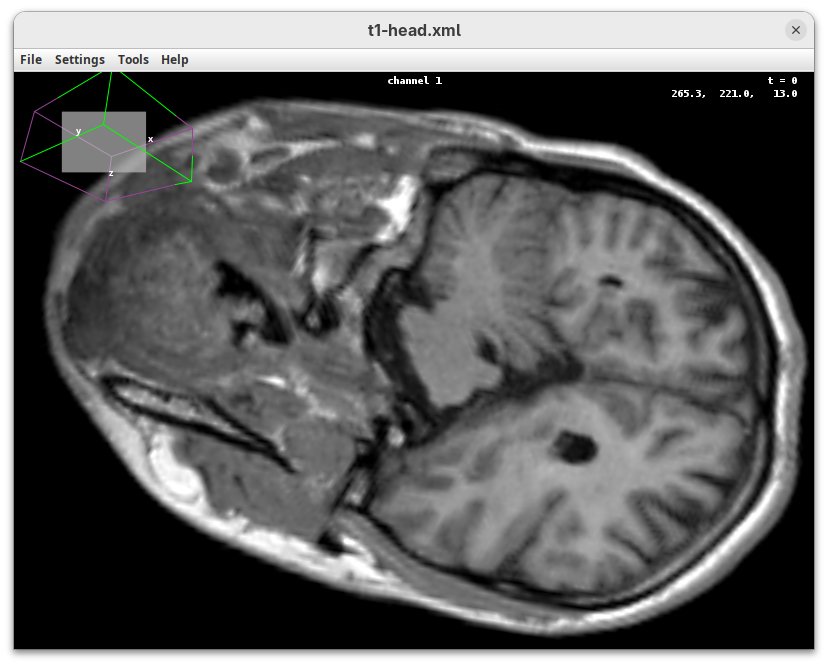

BigDataViewer (Pietzsch et al. 2015) is one of the most important tools for visualizing large, multidimensional datasets. It provides a simple and intuitive interface and shortcuts to swiftly navigate through your sample even on a regular laptop. This is possible because of the underlying file format used by BigDataViewer: the XML/HDF5 combo. Therefore, before opening the plugin, we must convert our dataset.

The BigDataViewer interface will open showing an optical section of the head sample.

Getting familiar with BigDataViewer is an essential skill for navigating large 3D datasets. It’ll also be important for the multiview registration pipeline. So, take the time to learn the basic commands and shortcuts. It is nicely intuitive. The BigDataViewer’s page on the ImageJ Docs has the official documentation and we can also go to Help > Show Help for an up-to-date overview.

Some of the movements to try:

Left-click and drag: turn the sample around the mouse pointer at any arbitrary angle.Right-click and drag: move the sample in the XY plane (of the view).Scroll: move through the Z plane (of the view). UseShift+Scrollto move fast.Ctrl+Shift+Scroll: zoom in or out.

But, most importantly, are the commands to put your sample back to its original orientation or along any of the original dimension axes:

Shift+Z: orient the sample on the XY plane.Shift+X: orient the sample on the ZY plane.Shift+Y: orient the sample on the ZX plane.

Finally, a visual tip. The default interpolation between image slices is nearest-neighbors. Press I to activate the tri-linear interpolation to obtain a much smoother (and improved) data visualization.